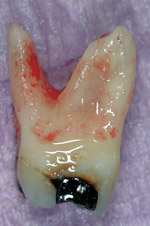

Fig. 7 Gouging typical of round bur-driven, cingulum-positioned access, likely compounded by insufficient magnification.

Figure 7